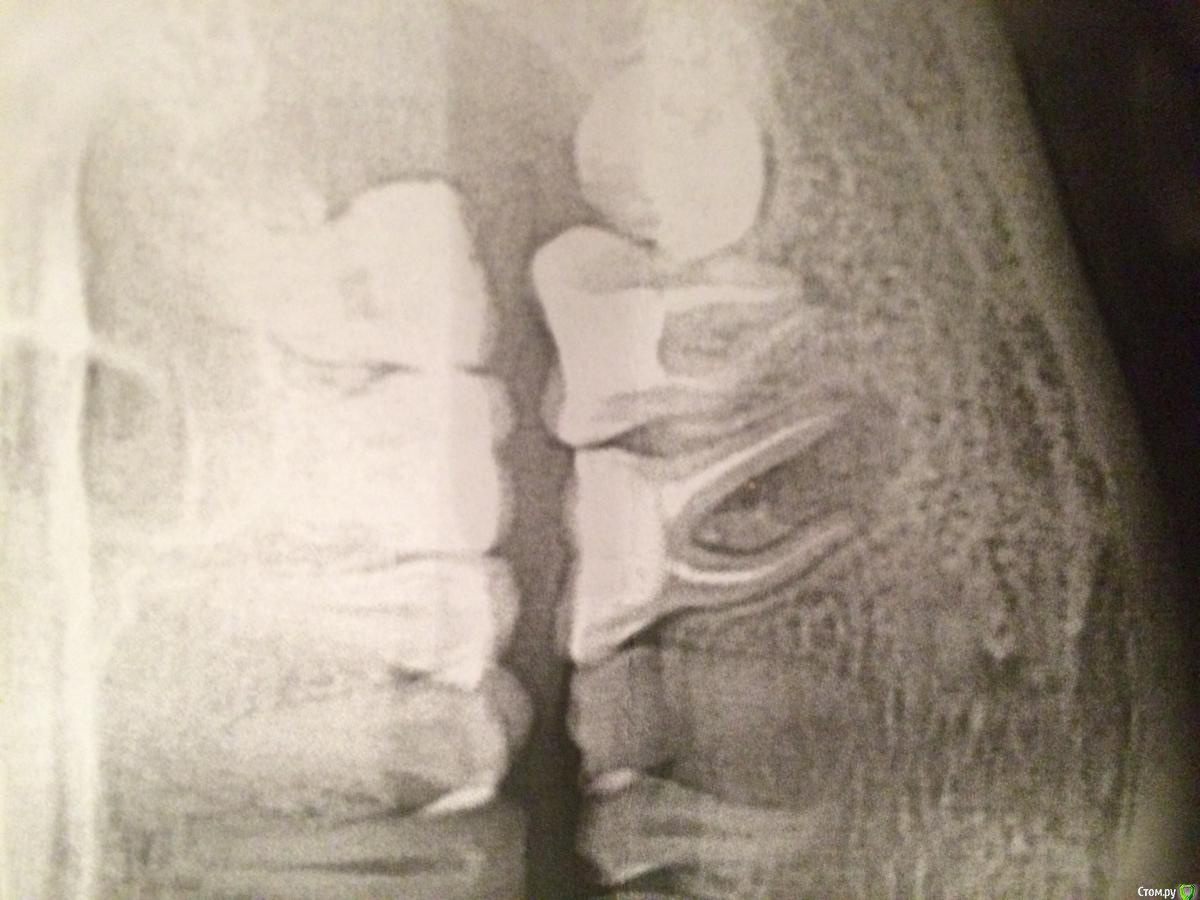

Dariadaria Опубликовано 13 сентября, 2015 Поделиться Опубликовано 13 сентября, 2015 Здравствуйте, дорогие! Обнаружили у меня большую кисту зуба. Хирург сказал, что надо удалять зуб с кистой, терапевт посоветовал попробовать сохранить зуб и лечить терапевтическими методами. Зуб стало жалко, поэтому решила попробовать вылечить. Терапевт что-то с этим зубом делал, не знаю что точно, поставил временную пломбу, через пару недель снова что-то делали, чистил каналы, потом вложил пасту(с содержанием йода, и привкус йода во рту присутствовал иногда в течение месяца), поставил пломбу, сказал через три месяца прийти. Интересно ваше мнение, как считаете, можно ли вылечить такую кисту или всё равно придется удалять? Поделитесь опытом)))Зуб шестерка слева(на снимке получается справа, вы это знаете, конечно, но на всякий случай Ссылка на комментарий

Dariadaria Опубликовано 13 сентября, 2015 Автор Поделиться Опубликовано 13 сентября, 2015 Вот снимок Ссылка на комментарий